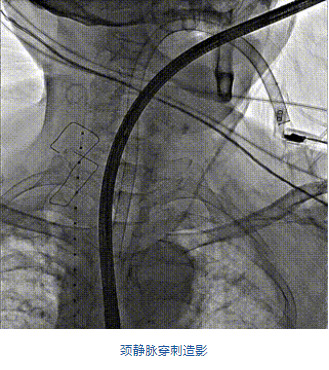

2022年5月27日,四川大學(xué)華西醫(yī)院心臟內(nèi)科陳茂、馮沅教授帶領(lǐng)的瓣膜病介入治療多學(xué)科團(tuán)隊(duì),在國(guó)內(nèi)首次采用純介入方式通過穿刺右側(cè)頸靜脈成功完成經(jīng)導(dǎo)管三尖瓣置換。植入的人工瓣膜是具有中國(guó)自主知識(shí)產(chǎn)權(quán)的LuX-Valve Plus系統(tǒng)。術(shù)中上海長(zhǎng)海醫(yī)院陸方林教授和喬帆副教授給予了在線支持。

團(tuán)隊(duì)前期經(jīng)過多次討論,制定了周密的手術(shù)策略和預(yù)案。由于患者已是近九旬的超高齡老人,傳統(tǒng)外科開胸手術(shù)風(fēng)險(xiǎn)極高,純介入經(jīng)血管三尖瓣替換能夠明顯減少創(chuàng)傷。術(shù)中陳茂及馮沅教授結(jié)合體表定位在造影指示下精準(zhǔn)穿刺右側(cè)頸靜脈并預(yù)置兩把血管縫合器。成功建立經(jīng)皮血管入路后在食道超聲和DSA的引導(dǎo)下順利完成人工瓣膜植入,術(shù)后超聲和造影顯示人工三尖瓣同軸性良好,瓣架固定牢靠,無反流和瓣周漏,平均跨瓣壓差降為1mmHg。術(shù)畢收緊預(yù)置的血管縫合器縫線完成止血,縫合效果滿意,在手術(shù)室即刻拔除氣管插管。